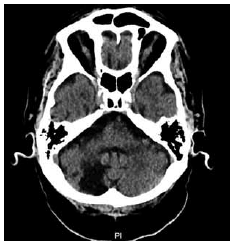

S.R.A., masculino, 84 anos, procura o ambulatório com queixas de tonturas que se iniciaram de forma súbita. As tonturas caracterizam-se por serem do tipo rotatórias associadas à turvação visual. Não há queixas de náuseas e vômitos, zumbidos nos ouvidos, escurecimento da vista, perda da consciência, convulsões e liberação esfincteriana. Entretanto, havia quedas frequentes conforme caminhava. Ao exame físico, nenhuma alteração foi observada exceto um nistagmo horizontal que se acentuava ao olhar para a direita. O paciente realizou uma tomografia computadorizada de crânio, mostrada a seguir:

Assinale a alternativa contendo o diagnóstico correto.